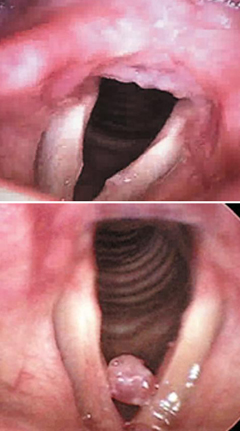

◇목: 성대결절= 큰 소리로 떠들거나 2차 노래방에서 고음으로 노래하면 성대는 평소보다 10배 이상 진동한다. 여기에 술을 마시면 체내 수분이 알코올 분해에 사용되기 때문에 성대가 건조해져 무리를 더 받는다. 그러면 성대 점막에 굳은살이 배기는 성대결절이 생긴다. 갑작스런 고성 한 번만으로 성대 점막의 가느다란 혈관이 터져 물혹인 성대폴립이 생길 수도 있다. 예송이비인후과 김형태 원장은 "성대폴립을 방치하면 몰혹이 점점 커져 호흡곤란을 겪을 수도 있다"고 말했다. 김 원장은 "송년회에서 쉰 목소리와 목 주변 통증이 2주 이상 지속되면 이비인후과에 가서 약물치료와 음성치료를 받아야 한다"며 "특히 성대폴립은 저절로 좋아지지 않으므로 레이저 수술로 제거해야 한다"고 말했다. ▶대처법= 2차로 노래방에 갈 때는 물을 한 병 사 가지고 가서 수시로 마신다. 맥주·커피·녹차는 성대를 마르게 하므로 삼간다. 날달걀이나 박하사탕은 성대 점막의 윤활유 분비를 막아 오히려 해롭다. 그 대신 대추차·생강차·배즙을 마신다.

후두내시경으로 본 성대결절(위)과 성대폴립. / 예송이비인후과 제공